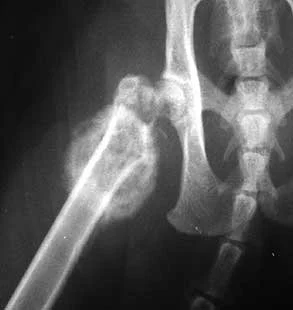

Care for the rabbit with osteosarcoma usually involves immediate pain control followed by diagnostic testing. Diagnosis of osteosarcoma usually begins with a to general anaesthetic to immobilise the rabbit, then X-Rays are taken of the painful area. If osteosarcoma is suspected from the radiograph, a chest radiograph may also be taken to see if the disease has spread to the lungs or other areas of the body. If there is no evidence of the disease spreading, a biopsy of the tissues (to extract some of the cells for microscopic examination) can confirm the diagnosis and help ensure that appropriate treatment is given.

As this disease is highly metastatic (spreads readily), rapid treatment is needed and even with treatment, survival may not extend more than a few months past diagnosis. Surgical removal of the tumour is the primary treatment and total limb amputation is common to remove all of the affected tissue. Amputation prevents the primary tumour from spreading, but it is not always a curative treatment since metastasis may have already occurred before any signs of disease. By the time the disease is diagnosed, invisible microscopic tumours may have already seeded in the lungs or other areas of the body.